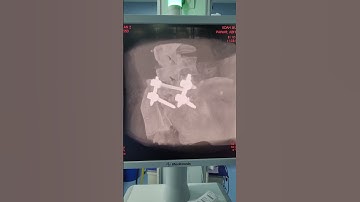

Minimally Invasive 3D Navigation Guided TLIF